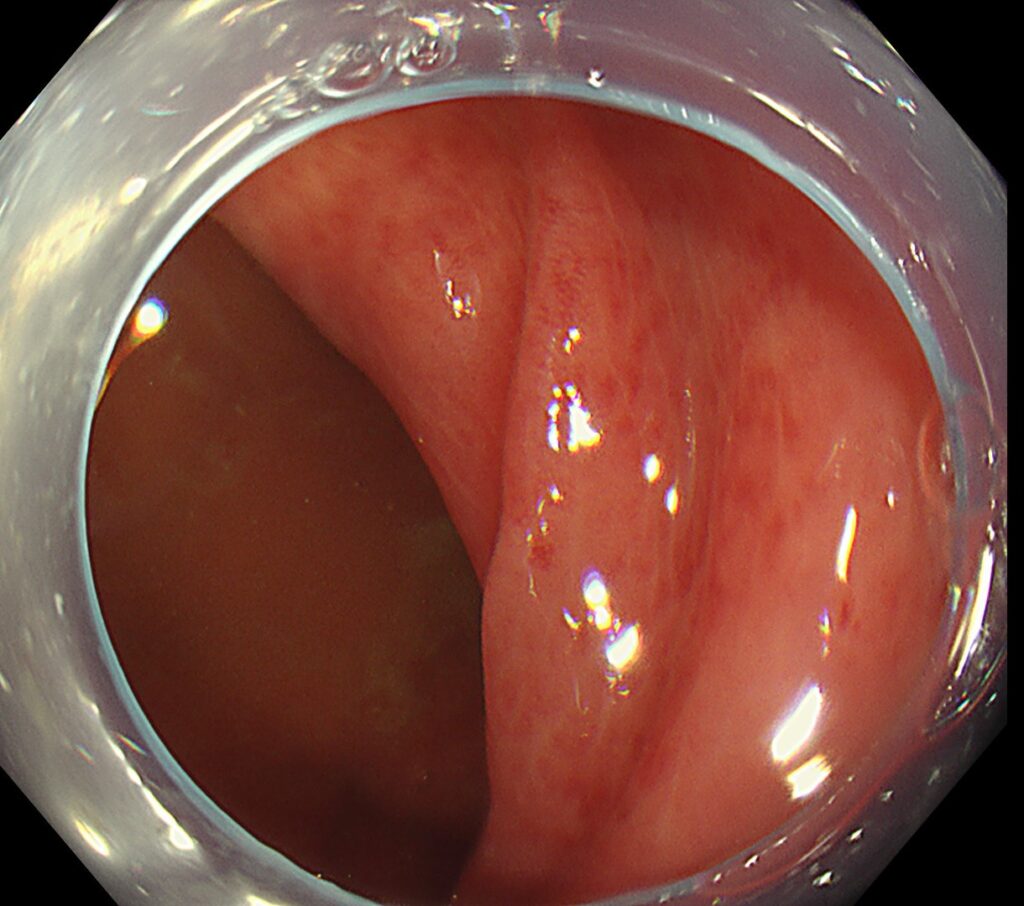

回腸末端に縦走する多発潰瘍を認めます。